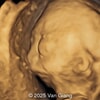

A 34-year-old woman, G2P1001, presented to our maternal fetal medicine unit at 30 weeks of gestation for a late fetal anatomic survey. The fetus was female with low-risk noninvasive prenatal testing. The following findings were observed.